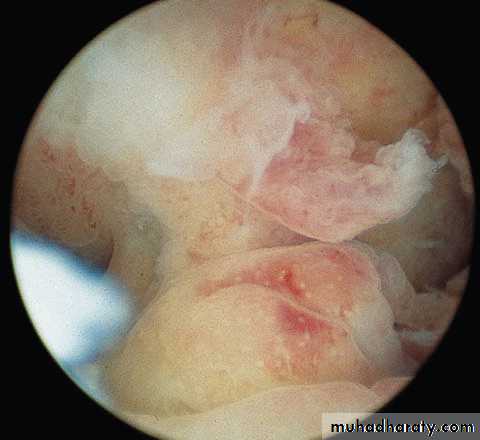

A 48 YR OLD LADY HAS MENORRHAGIA NOT RESPONDING TO MEDICAL TREATMENT

1.WHAT IS THE SURGICAL PROCEDURE

SHOWN ?

2. LIST 3 COMPLICATIONS